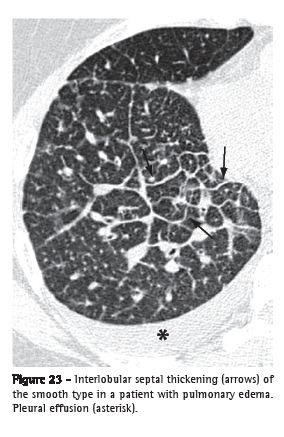

Interlobular septal thickening (espessamento de septos interlobulares)

Interlobular septal thickening is the thickening of the connective tissue septa separating the secondary pulmonary lobules. It is radiographically characterized by thin linear opacities, also designated Kerley B lines. It is usually in close contact with the lateral pleural surface, near the costophrenic sulci, at a right angle to the pleural wall. Currently, the terms "septal lines" or "septal thickening" have gained favor over Kerley lines. On HRCT scans (Figure 23), the thickening of the interlobular septa is characterized by the presence of linear opacities that delimit the secondary pulmonary lobules, more easily characterized in the subpleural region, in which it has the aspect of lines at right angles to the pleural surface.(3,44) In the central regions of the lungs, the thickening of the septa of adjacent lobules results in the aspect of polygonal arches. Septal thickening can be secondary to changes in any of its components (veins, lymphatic vessels or connective tissue) and is a finding common to various lung alterations; however, its presence is particularly highlighted in cases of pulmonary edema and lymphangitic carcinomatosis. Septal thickening can be smooth (Figure 23), nodular (Figure 24) or irregular. This differentiation can aid in the differential diagnosis.

Secondary pulmonary lobule (lóbulo pulmonar secundário)The secondary pulmonary lobule is the smallest anatomic unit of lung delimited by a septum of connective tissue. It is polyhedral in shape, measures 1.0-2.5 cm in diameter and contains a variable number of acini.(45) The center of the lobule is formed by the bronchiole and its accompanying pulmonary artery, lymphatic vessels and adjacent interstitium. In its periphery, the connective tissue forms thin septa designated interlobular septa, which contain small pulmonary veins and lymphatic vessels (Figure 25). In normal patients, the interlobular septa are better identified in the anterior, lateral and paramediastinal peripheral regions of the upper and middle lobes, as well as in the peripheral region of the anterior diaphragmatic region of the lower lobes, tending to be incomplete or absent in the remaining lung regions. The interlobular septa are easily recognized on HRCT scans when the septal interstitium is affected (Figures 23 and 24).(3)